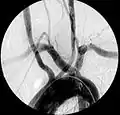

| Aberrant subclavian artery on MR angiography. | |

Aberrant right subclavian artery at angiography.